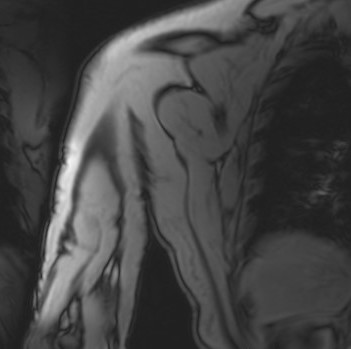

Ante estos hallazgos sin saber concretar la naturaleza clara de la lesión, se solicita una resonancia magnética (RMN) preferente. La RMN informa de una lesión homogénea, bien definida, dependiente del músculo coracobraquial, de 35 × 18 × 82 mm, con finos septos internos sin engrosamientos nodulares, compatible con lipoma intramuscular.

El principal diagnóstico diferencial es el liposarcoma, especialmente por el tamaño y localización profunda. La ausencia de engrosamientos nodulares y la homogeneidad en la imagen apoyan la benignidad.